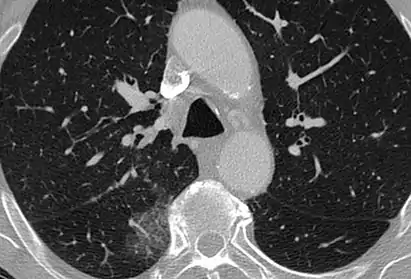

- InfluenzaCT image showing ground-glass opacification in the posterior of the right lung (screen left).

- Lung adenocarcinomaCT image showing diffuse GGOs throughout both lungs. An abscess is also noted in the right lung (screen left).